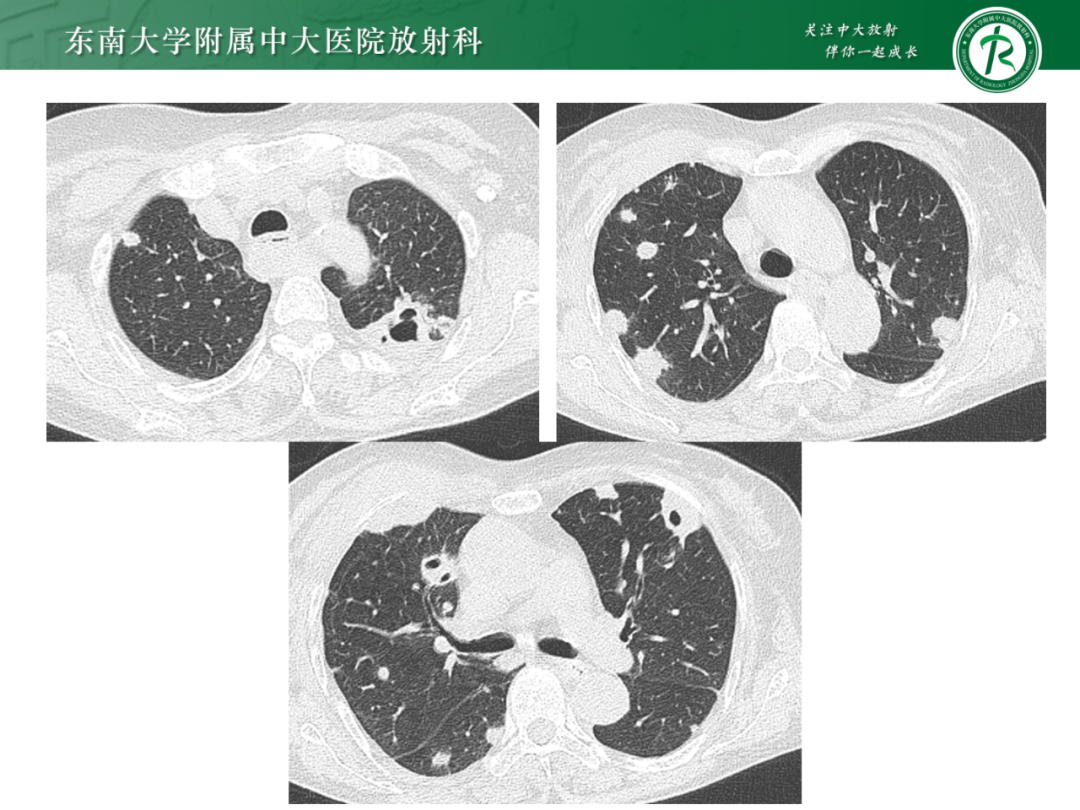

肺多发空洞病例分析|今日病例

作者:东南大学附属中大医院 吕文晖

来源:东南大学附属中大医院放射科